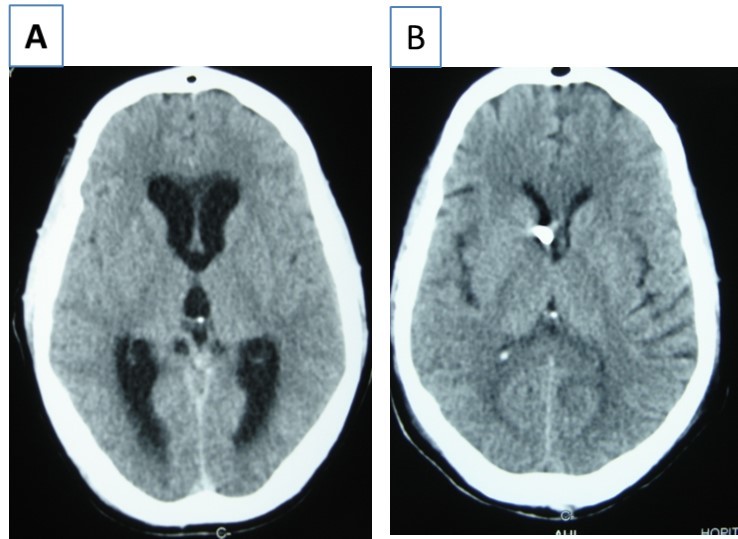

Patient was placed on intra veinous amphotéricin B but this was complicated with acute active hydrocephalus warranting external ventricular drainage (Figure 3). Subsequently, he developped staphylococcal meningitis as day 8 post op, treated with intra veinous vancomycin. Patient developed renal insufficiency and hyperosmolar non ketotic coma for an unknown diabetis for which amphotéricine B therapy was stopped. His neurological status deteriorated with a Glasgow coma scale (GCS)7/15. Posterior fossa surgery was performed with excision of the fungal abscess (Figure 4) and Voriconazol was instituded post operatively for fungal therapy with improvement of the neurological status to GCS 13/15. But the patient succumbed to acute cardiac failure.

Figure 3.cerebral CT scan with axial view showing acute hydrocephalus (A) and control after external ventricular drainage (B)

Figure 4.cerebral CT scan pre operative (A) and post operative (B) after posterior fossa surgery with total removal or abscesses